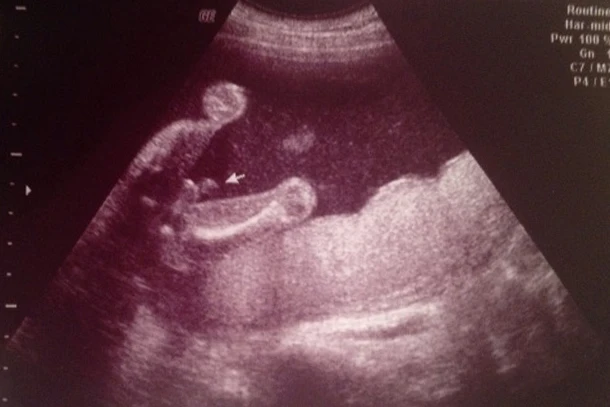

3 линии – пример за девојче

– Сликата подолу е скенирање од жена во 20. недела од бременоста и јасно се прикажани трите линии. Кога сонографот ќе покаже зошто мисли дека е девојче, ќе ги искористи овие три линии како илустрација – вели Стујард.